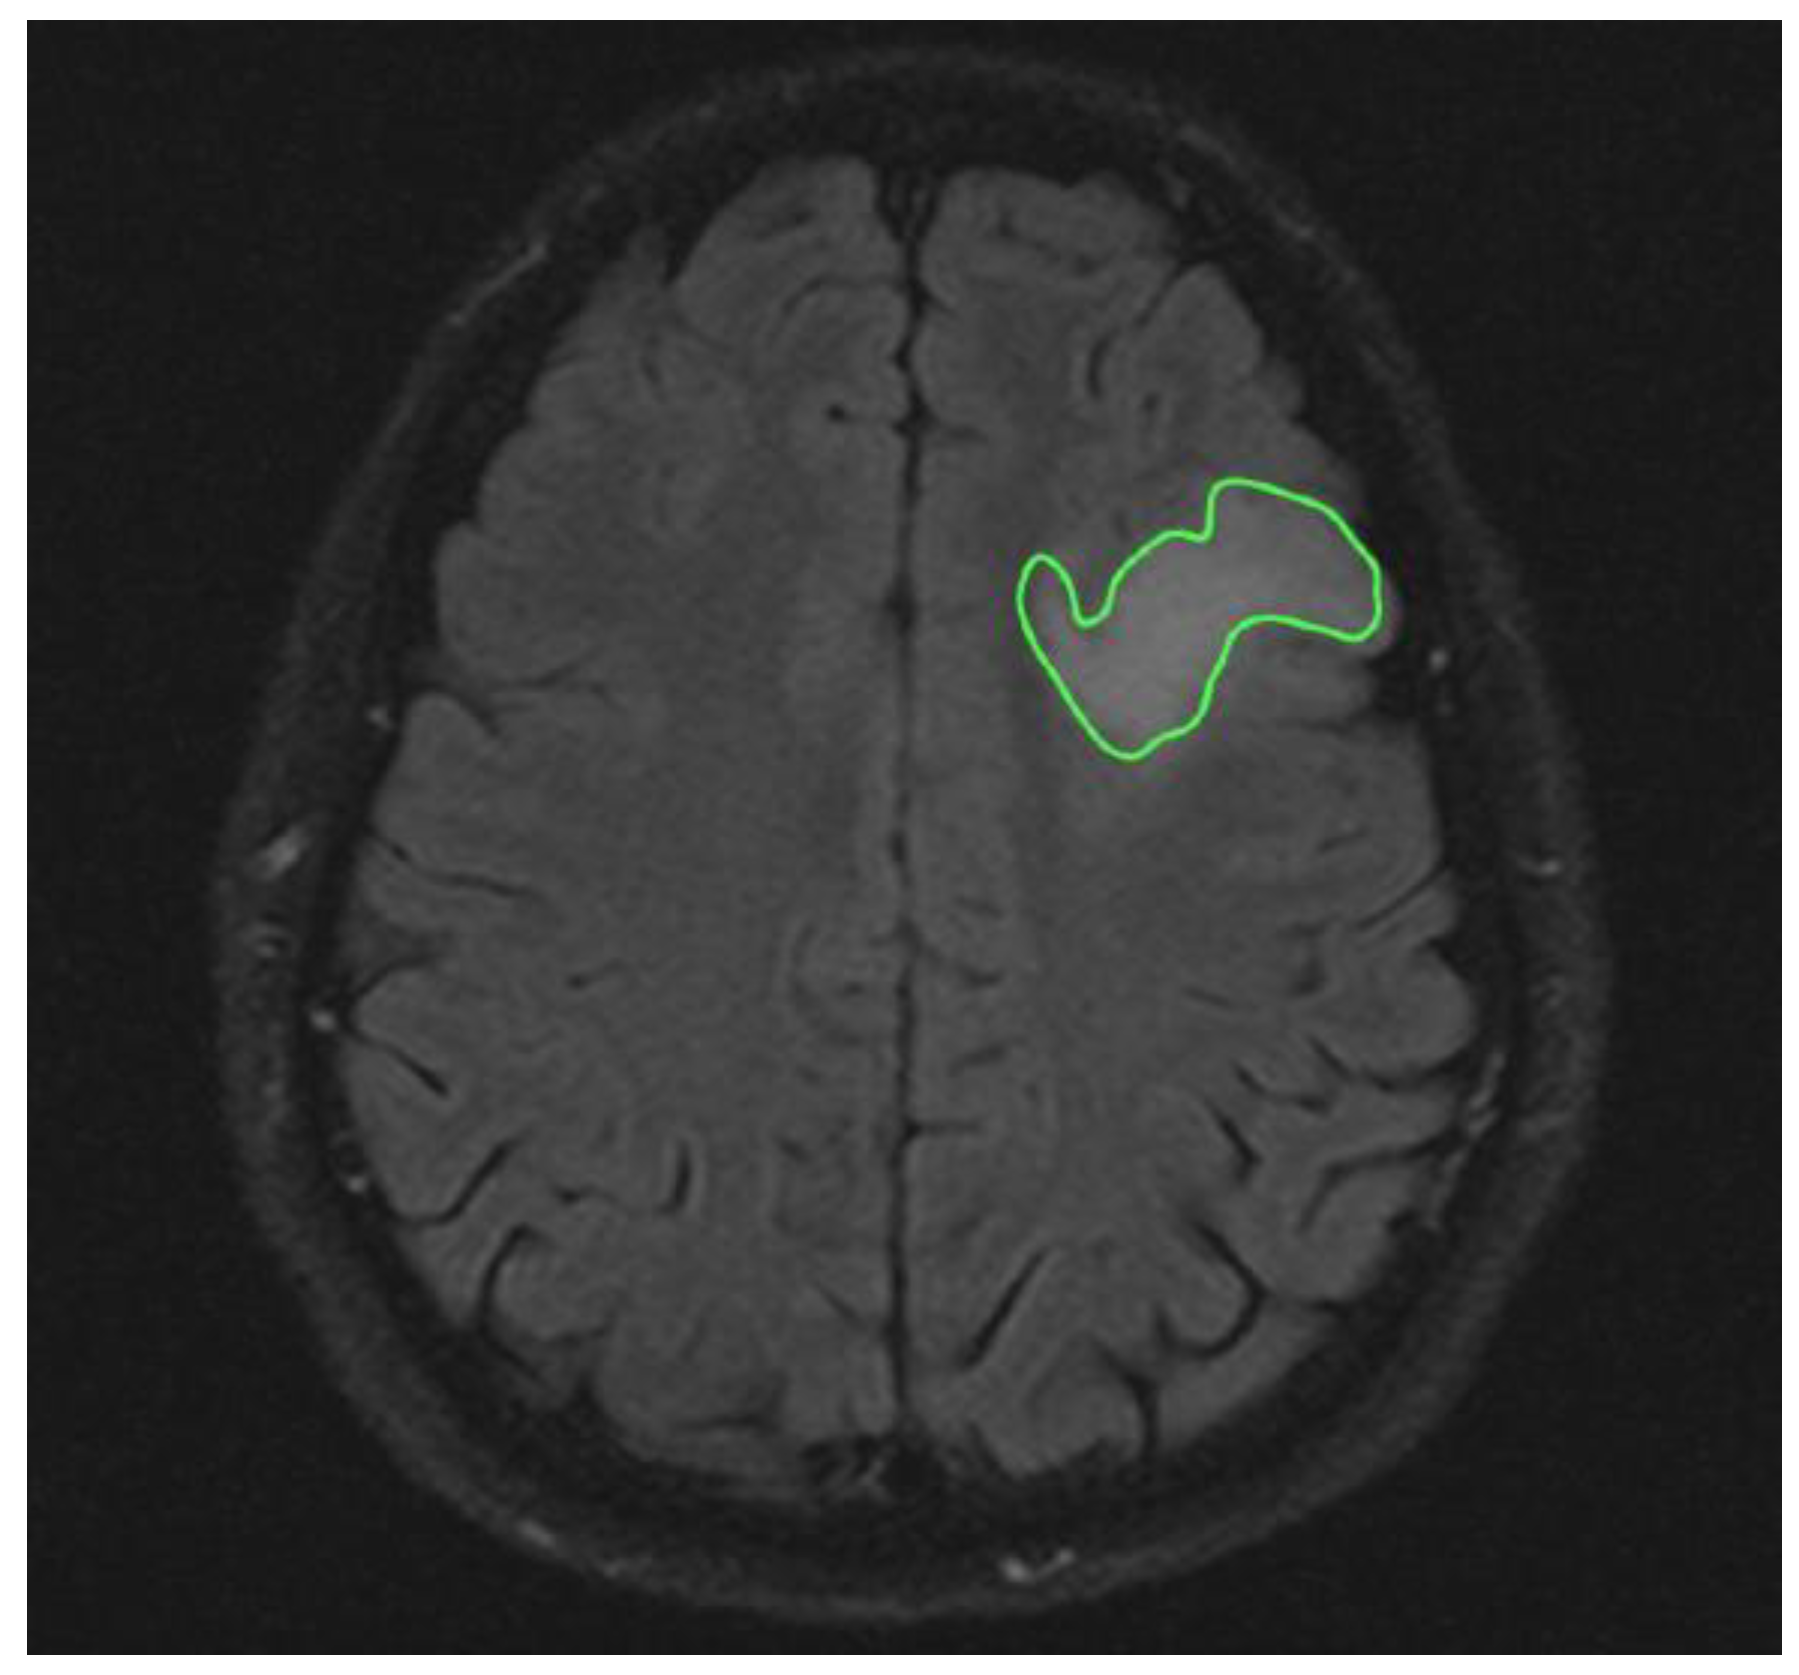

| Group 3 Tumor volume MRi Flair | 18.06 ± 4.4 cm3 |